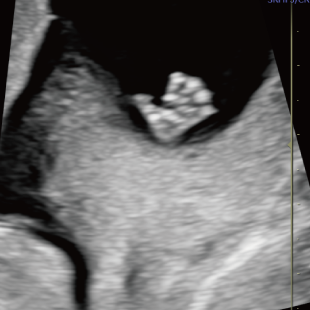

赤ちゃんの3~5%は、何らかの病気や医学的な介入を要する状態をもって生まれてくるといわれており、その中には、妊娠中・出生時・出生後に緊急の対応を要するものも含まれます。 特に先天性心疾患は比較的頻度が高く、約100人に1人の赤ちゃんが先天性心疾患を合併し、重症度や緊急性の高い症例(生後に入院や手術が必要な症例)は約1000人に4人といわれています。